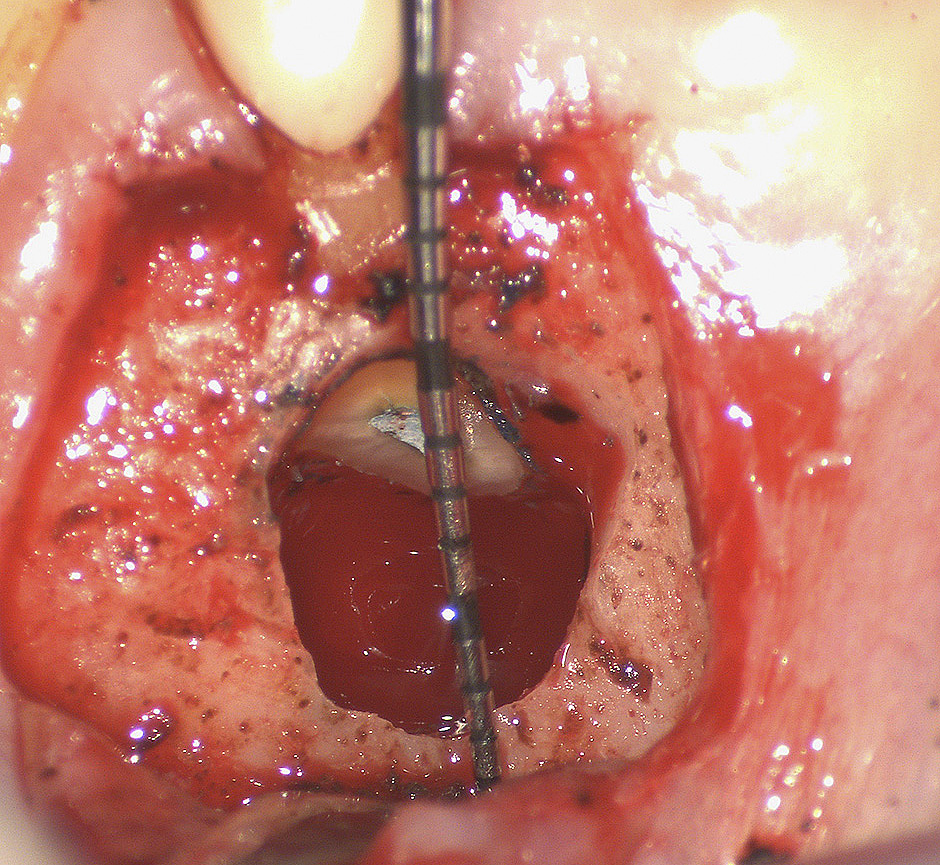

In chirurgia endodontica (apicectomie) il microscopio operatorio permette di individuare, osservare e curare ciò che ad occhio nudo o con ingrandimenti minori sarebbe impossibile vedere, mettendo in evidenza ogni piccolo particolare in modo chiaro ed evidente e di conseguenza alzando notevolmente il livello di cure e quindi di probabilità di successo al termine delle nostre terapie.